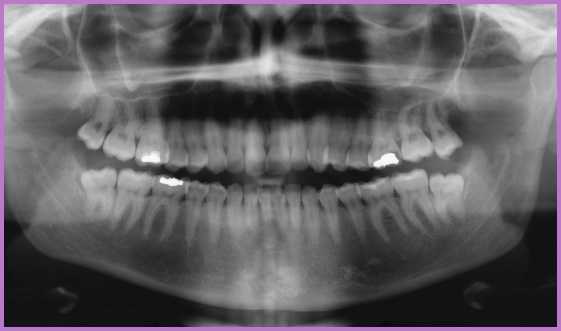

Honlapunk egyik specialitása, hogy online is kérhet kezelési tervet, amennyiben el tud küldeni számunkra egy panoráma- vagy intraorális röntgenfelvételt.

Szakorvosaink megírják, hogy a felvétel alapján milyen beavatkozás(ok) indokolt(ak), ám az is előfordulhat, hogy a röntgenkép alapján még nem hozható egyértelmű döntés.

Ilyenkor a fogorvos személyes felkeresése javasolt. A konzultációra feltétlenül vigye magával régi felvételét, ám készüljön fel arra, hogy a szakorvos újabb felvételeket javasolhat, ha a régi felvétel nem használható, vagy a diagnózishoz kiegészítő felvételekre is szükség van. Bonyolultabb esetekben akár szakorvosi konzultációra is tehet javaslatot a kezelőorvosa.